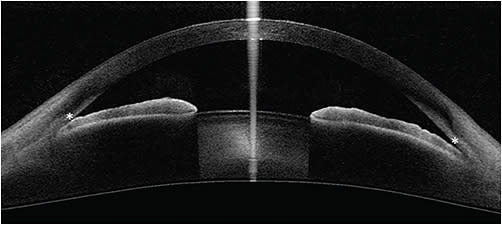

Potential clinical uses of AS-OCT include distinguishing open from closed angles, evaluating risk factors that may contribute to angle closure or predict progression to glaucoma, and assessing the effects of therapeutic interventions. Qualitative definitions and quantitative parameters have been established to allow evaluation of OCT for these purposes. A closed angle is one in which there is iridocorneal contact anterior to the SS (Figure 1).5,8 For quantitative assessment of the angle, an assumption is made that the trabecular meshwork is located approximately 500 µm to 750 µm anterior to the SS, and this is the basis for the parameters of the angle opening distance (AOD) 500 and 750, trabecular iris space area (TISA) 500 and 750, and angle recess area (Figure 2).4 Additional measurements of the anterior chamber (eg, anterior-chamber depth and width), lens (eg, lens vault [LV]), and iris (eg, iris thickness, iris curvature) have been defined as well.9 Multiple studies have evaluated the agreement of these parameters between different OCT devices. Angle measurements tend to be correlated but have poor agreement when time-domain and spectral-domain devices are compared with swept-source; therefore, they are not considered interchangeable.7,10-12